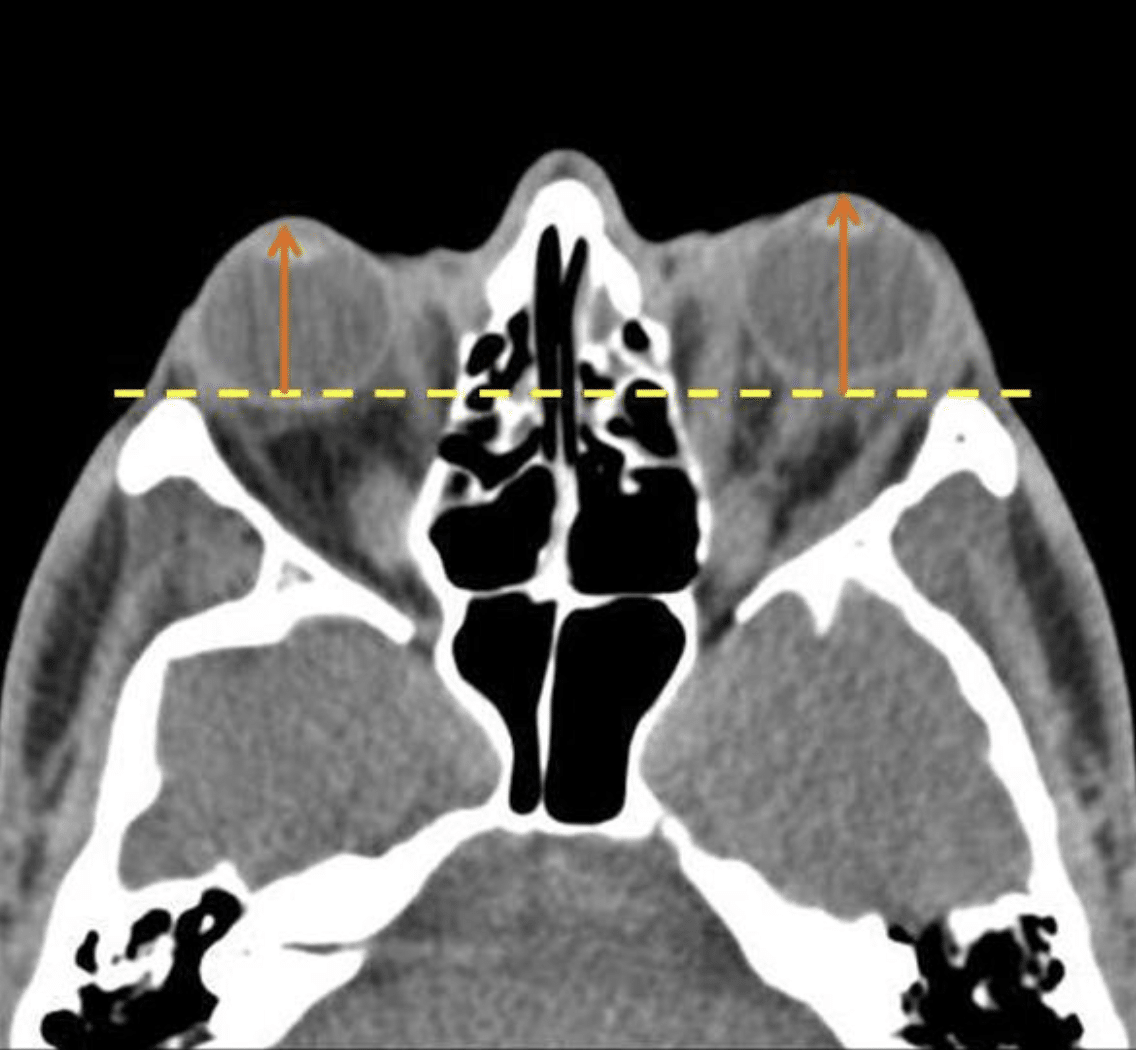

Axial CT images and at a level of the lens. If the distance from the anterior margin of the globe to interzygomatic line exceeds 21 mm, it is compatible with proptosis. In the case above the distance from anterior margin of the globe to interzygomatic line is 23 mm (right) and 25 mm (left). The findings are compatible with ocular proptosis due to thyroid ophthalmopathy.